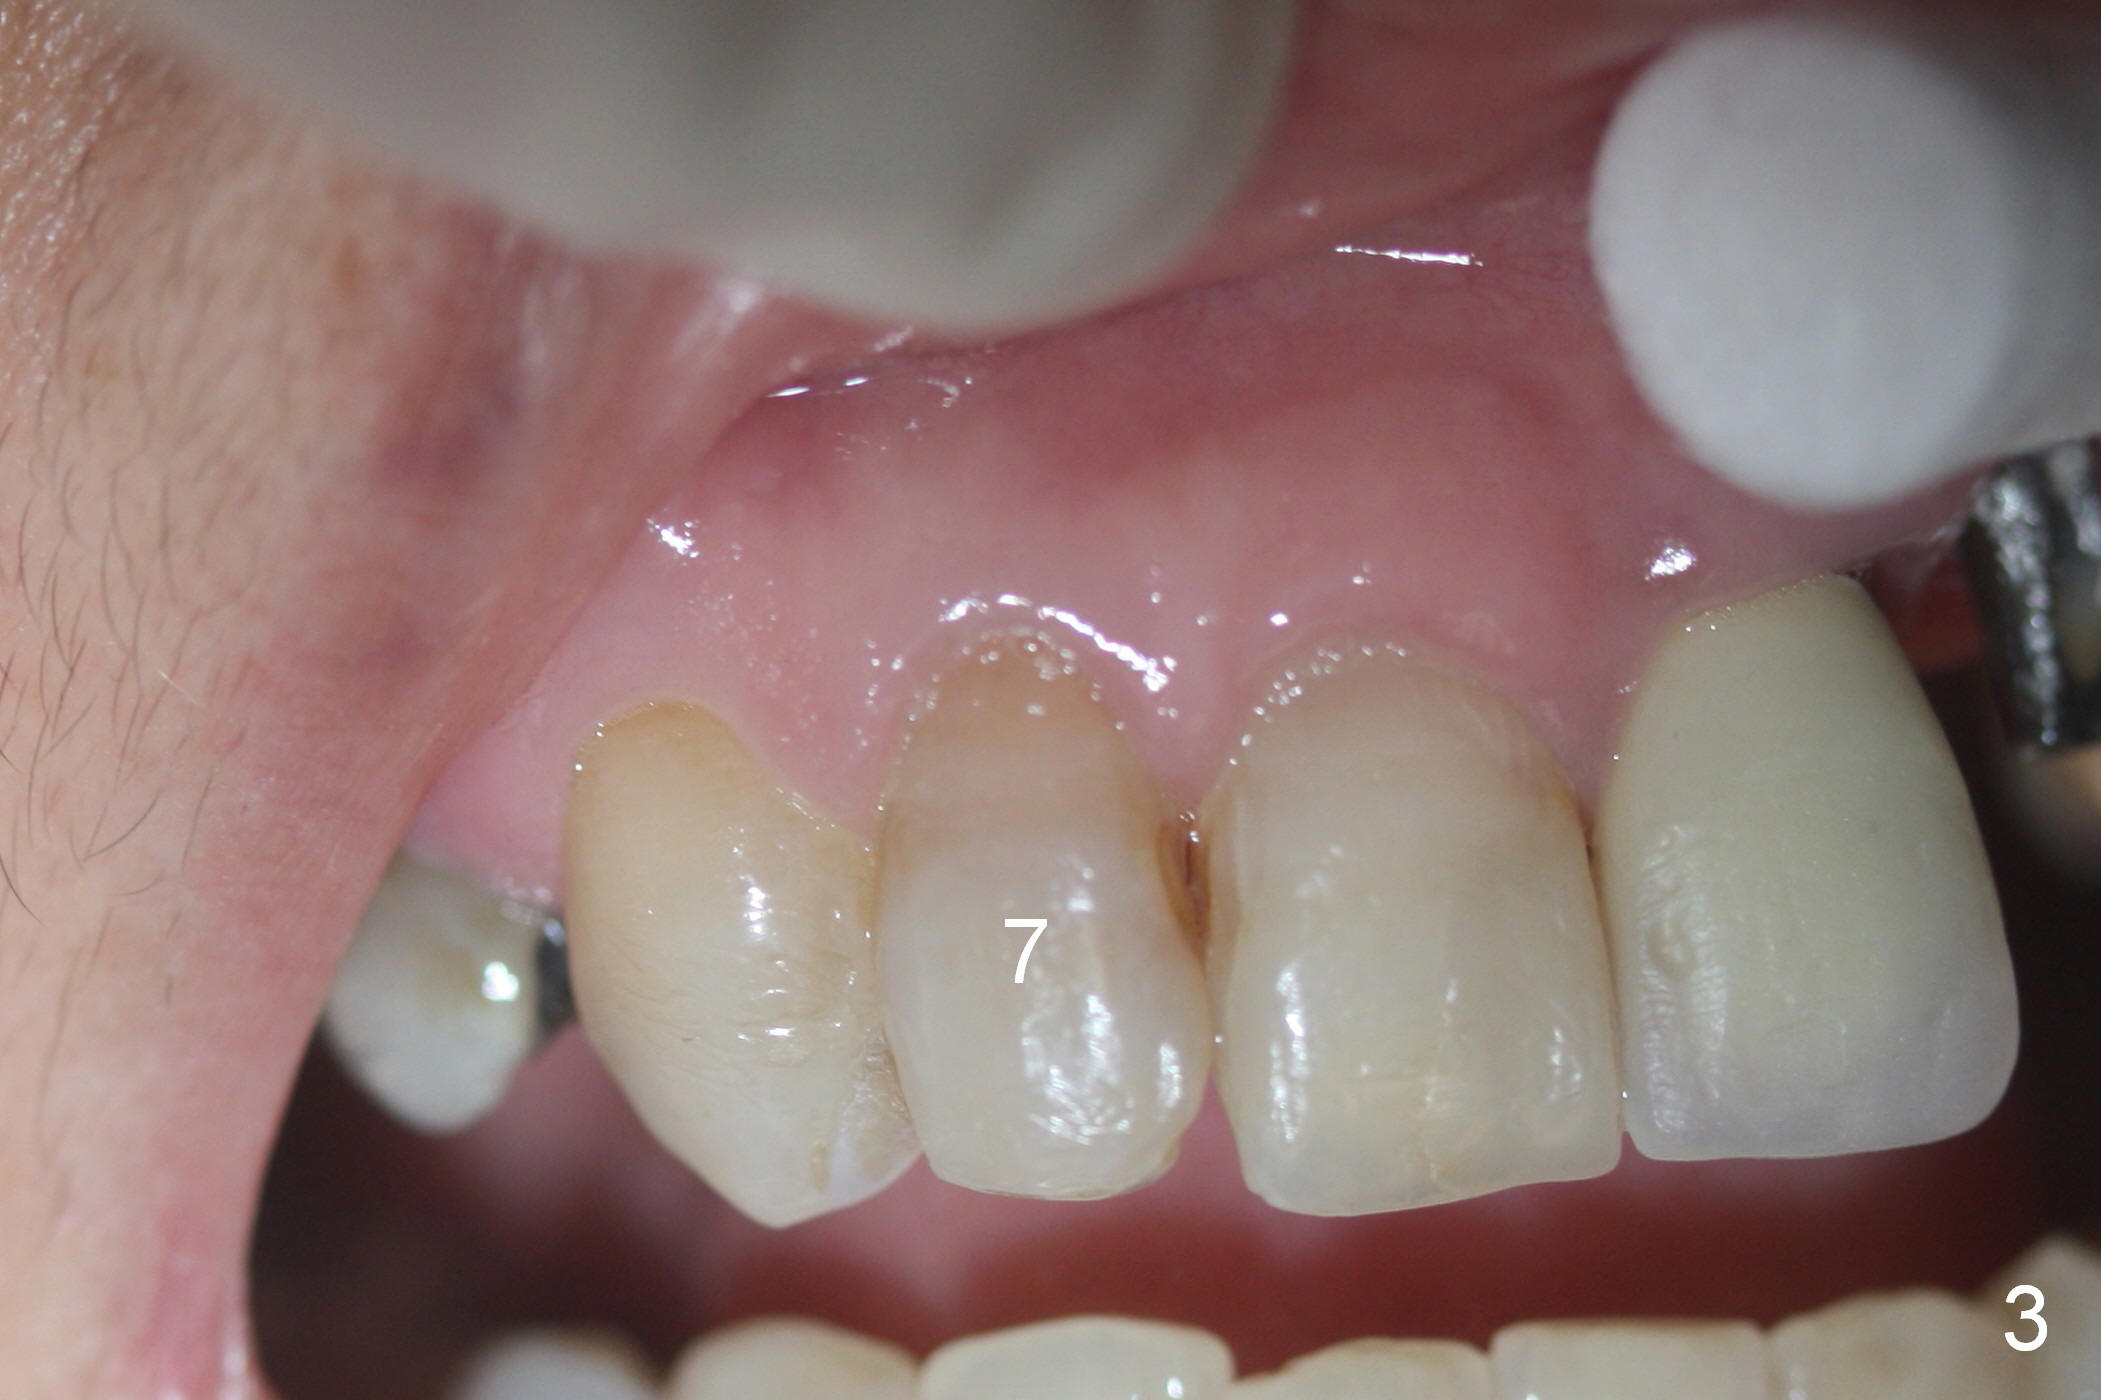

Close Mesial Gingival Embrasure

Mrs. Chen likes the shape of the temporary crown (Fig.1), particularly the mesial portion (arrowheads). Change the shape of the permanent crown (Fig.2 arrowheads) to alleviate the problem of papillary recession. Use the tooth #7 as a reference (Fig.3).